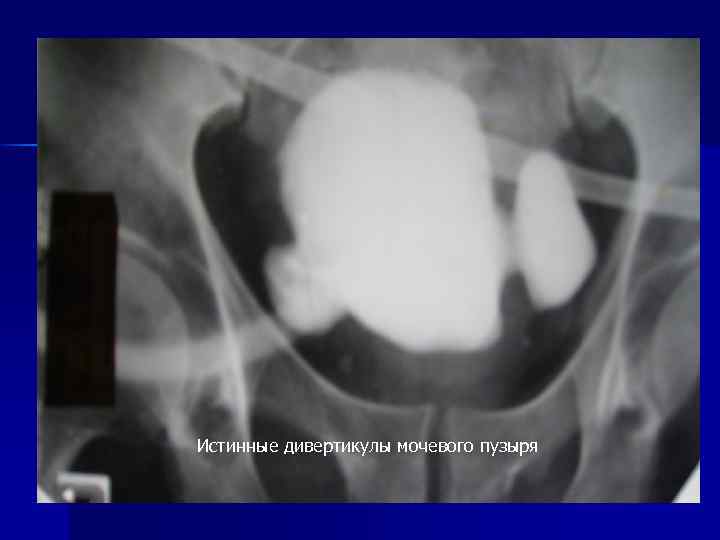

Истинные дивертикулы мочевого пузыря